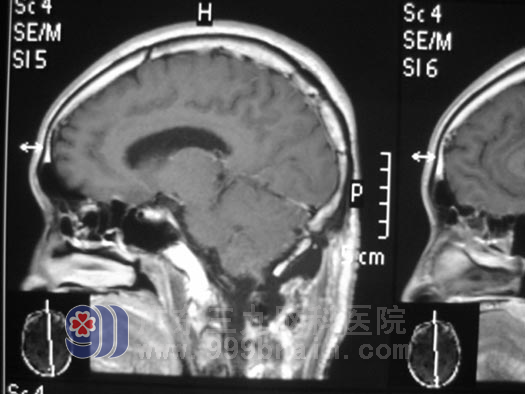

手术后

一个多星期过去了,叶先生恢复的很好,未再出现过头晕头痛、呕吐症状。叶先生的妻子一颗忐忑不安的心终于踏实下来。叶先生出院那天,其妻子带了好多礼物要送给鲁明 主任,都被鲁明 主任婉言谢绝了,他淡淡地说:“作为一名医生,为患者解除痛苦是我的天职,能把病人治好就是对我最大的欣尉了。”www.999brain.com

据神经外五科 鲁明 主任介绍,此次手术为叶先生一下子解决了左侧小脑占位、梗阻性脑积水、小脑扁桃体下疝畸形三个问题。为了避免术后小脑创面水肿,小脑体积增大,出现小脑扁桃体下疝,避免术后再次出现小脑扁桃体下疝压迫延髓而威胁生命,鲁明 主任为叶先生实施了寰椎减压术;并于手术中行颅内压探头置入术,以便捷地了解手术后颅内压力的变化,术后复查MR显示占位全切,术后病理回报为:左侧小脑半球血管母细胞瘤。www.999brain.com